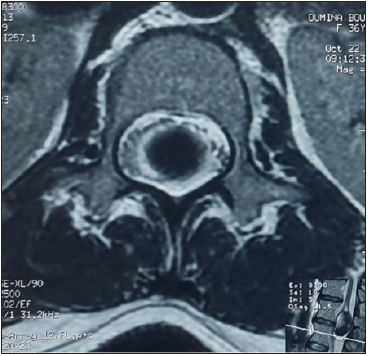

A 37-year-old woman presenting with low backache, and progressive weakness of both lower limbs for 5 months. On clinical examination, she had features of a conus medullaris syndrome with grade 4 power in both lower limbs, positive Babinski sign bilaterally, while abdominal reflexes and anal tone were normal without tuft of hair or a patent dermal sinus tract. A magnetic resonance imaging MRI showed cord expansion at the tip of the conus medullaris with a heterogeneous lesion hyperintense on T1 and hypointense on T2 images. In addition, contrast enhanced images with gadolinium revealed an intramedullary lesion at T12 L1 segment (Figure 1). After laminectomy, a midline myelotomy was performed and revealed a whitish and yellowish mass with a well-defined adherent capsule to spinal tissue followed by micro-dissection of the cyst wall allowing complete removal of caseous cystic contents with adequate conus decompression (Figure 2). Pathological examination confirmed the diagnosis of dermoid tumor, showing stratified squamous epithelial cells with underlying fibrous connective tissue containing hair follicles, keratin and sebaceous glands. The patient recovered well from the procedure, her back pain had not recurred, and she remained independent postoperatively.

Figure 1c: Spinal MRI sagittal T1 (a), T1 postcontrast (b) and axial T2 (c) showing an heterogenous lesion hyperintense T1, hypointense T2 of the conus at T12 L1 level.